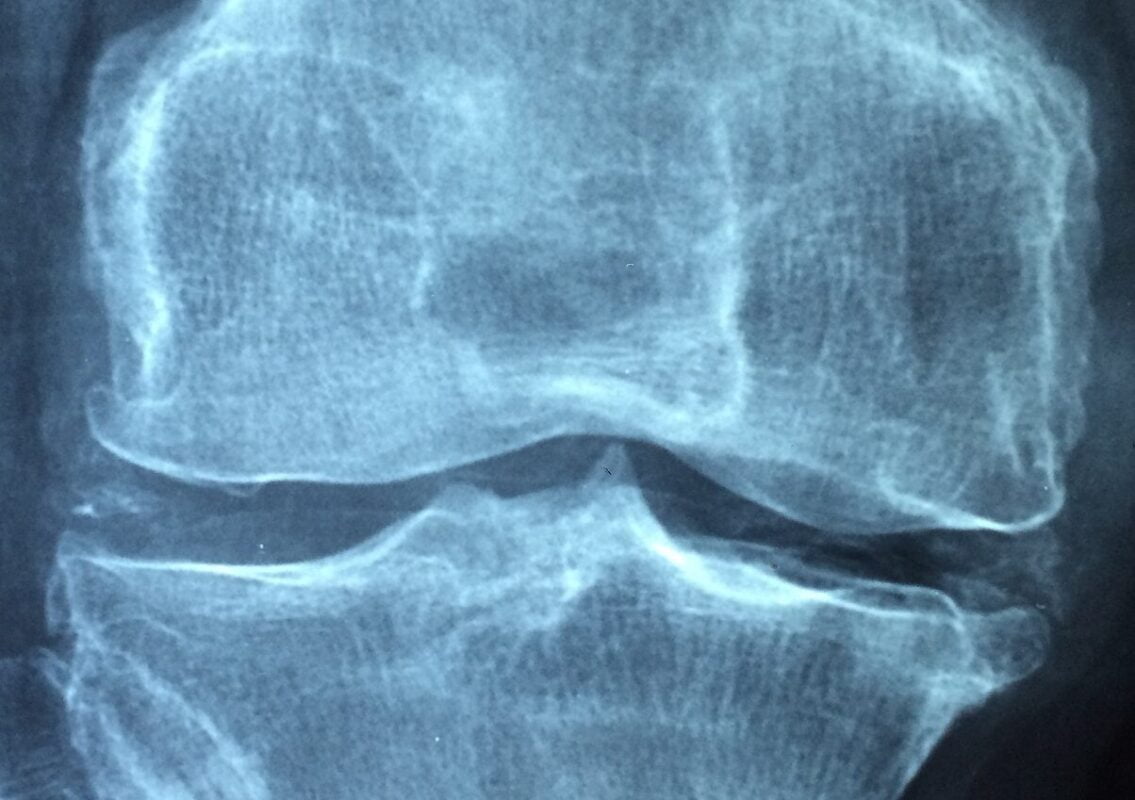

Tipos de Artralgia: Osteoartritis e Inflamatoria. Foto por Taokinesis Pixabay

Uno de los tipos más comunes de artralgia es la osteoartritis (3). Esta es una enfermedad de junta degenerativa, en la cual se ve afectado el cartílago que se encuentra situado a los extremos de los huesos, en las juntas, para facilitar la realización de movimientos suaves y sin dolor (3).

El riesgo de padecer osteoartritis aumenta con la edad. El uso continuado puede hacer que el cartílago se irrite, produciendo dolor e inflamación (3). Asimismo, la baja progresiva del cartílago hace que los extremos de los huesos se vean sometidos a la fricción, que conduce a una disminución de la movilidad común (3).

El dolor que se manifiesta por este tipo de artralgia suele venir dado al final del día o después de la actividad física. También puede existir rigidez durante las mañanas y después de períodos de inactividad (3).

El diagnóstico de la artralgia comienza con un examen físico y una revisión de los síntomas del paciente (2). También puede incluir pruebas de laboratorio y pruebas de imagen como rayos X, resonancias magnéticas (MRI) y ultrasonidos (2). Estas pruebas pueden ayudar a identificar la causa del dolor y a descartar otras condiciones médicas (2).